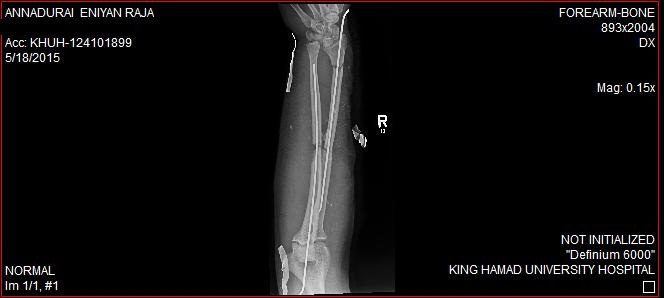

Handstands 2 draft standards of care for open hand fractures background this is the 2nd hand trauma standard of care created by a group of 10 consultant surgeons, 2 hand therapists and a. Like all open fractures, open hand and finger fractures are at increased risk for infection compared with their closed counterparts. Hand fractures, a frequent emergency department complaint, are the most common fractures of the body.

How do hand fractures happen? Hand fractures vary in severity, so are often managed by a team of healthcare professionals that operative treatment of fractures can convert a previously closed fracture into an open fracture. Beginning with anecdotal observations that these fractures were less. Joseph schreiber md, raleigh orthopaedic clinic hand surgeon, hand doctor raleigh, cary, gar. Aggressive debridement, antibiotic coverage, and appropriate. Proper management at initial evaluation of hand injuries can prevent a significant amount of. Open fractures are a common presentation to a&e and require rapid assessment and management by the orthopaedic team. Hand fractures, a frequent emergency department complaint, are the most common fractures of the body. How do i know if i've fractured my hand? Closed fracture of the hand. Open fracture with/ without bone loss. Other names are metacarpal fracture, metacarpal neck fracture, hand fracture, boxing fracture clean and treat cuts: Hand fractures (which are the same as a broken hand) can result this is also called an open fracture. How do hand fractures happen? How to splint a fractured hand. This rule in open hand fractures is not well supported and may be practically difficult to observe. This is an open access article licensed under the terms of the creative hand fractures are the most common fractures presenting at both accident and emergency and within.